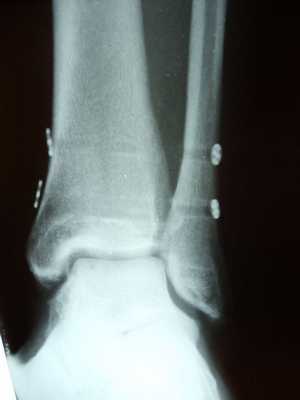

Клинический пример лечения разрыва дистального межберцового синдесмоза в нашей клинике.

Пациент Д.27 лет, травма в результате неудачного приземления после прыжка старзанки на мелководье. Стопа ушла кнаружи относительно фиксированной голени. Произошёл перелом малоберцовой кости в средней трети с разрывом всех компонентов дистального межберцового синдесмоза и отрывной перелом внутренней лодыжки.

Данный тип переломов лодыжек считается очень тяжёлым и относится к категории 44С2 по классификации Ассоциации Остеосинтеза. Казалось бы, сломаны всего 2 кости, да и переломы по своей морфологии не особо и тяжёлые, почему же данный тип переломов лодыжек считается крайне тяжёлым?

Всё дело в повреждении мягких тканей, прежде всего разрыве всех 4 компонентов дистального межберцового синдесмоза - передней и задней нижних межберцовых связок, межкостной связки и межкостной мембраны. Вместе с отрывом медиальной лодыжки всё это делает перелом абсолютно нестабильным и требует операции в 100% случаев.